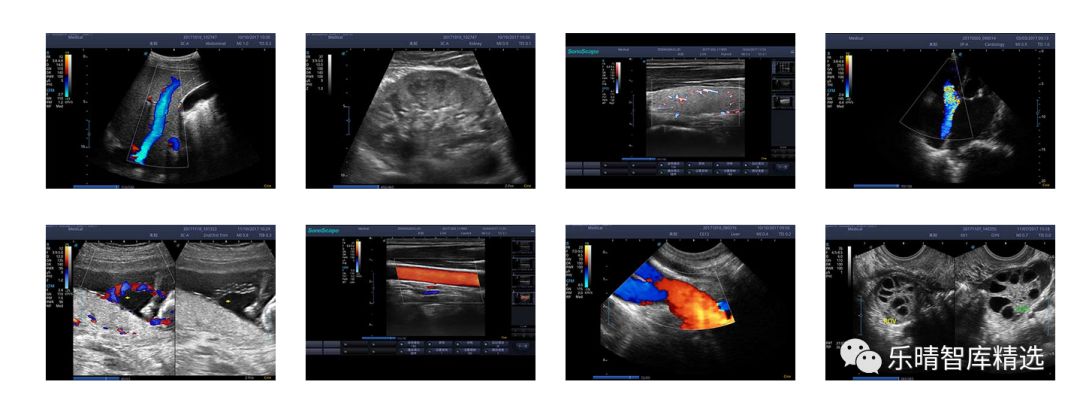

广义的医学影像学包括四大类,同位素扫描、CT、核磁、超声是现代医学影像诊断学的四大基石。不同的影像诊断手段有各自的优劣势,相互补充和彼此印证。其中超声(UltrasonicMedicine)作为诊断的一种常规手段,由于其便利、无创、图像实时,被广泛应用,目前超声设备已经成为无人不晓的诊断方式。

随着超声应用领域的逐步拓展,满足不同临床需求的特定超声不断出现,超声的应用场景日渐丰富,“超声+”的概念成为主流。